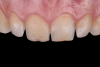

Fig 1. Preoperative intraoral view; maxillary incisors and canines are to be restored with ceramic laminate veneers.

Figure 1